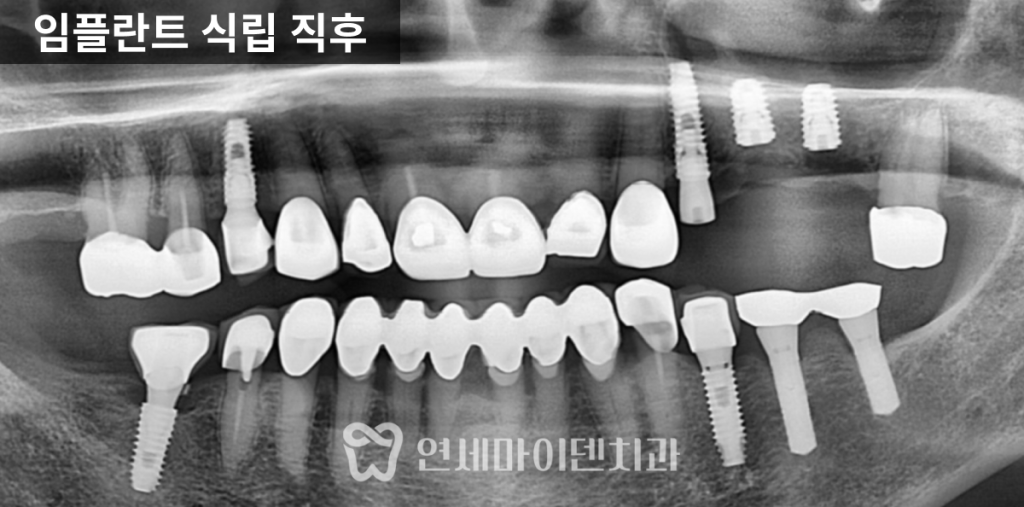

빠른 판단이 필요합니다.치료 전 상태: 뼈가 거의 없는 상황

이번 환자분은

오른쪽 위 어금니는 심하게 흔들리는 상태였고

아래 왼쪽 어금니는 발치 후 오래 방치되었습니다.

CT를 확인해보니

뼈가 거의 남아 있지 않았고,

손으로도 발치가 가능할 정도였습니다.이 상태를 오래 두면

4년 경과: 결과는?

이번 케이스는

4년이 지난 현재까지✔ 임플란트 안정적 유지

✔ 주변 치아 뼈 레벨 유지

✔ 정기 관리 지속임플란트의 수명은